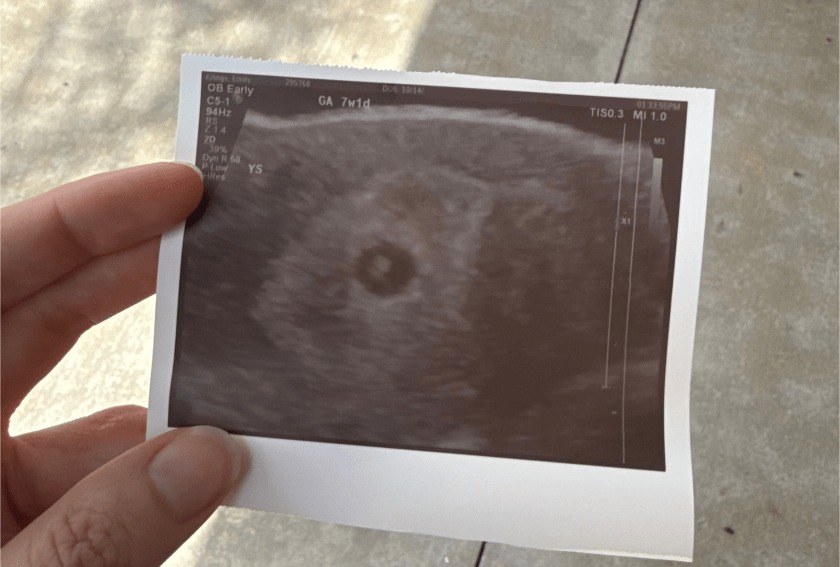

Ultrasound at 7 weeks

We went for the ultrasound, and the tech confirmed that the pregnancy was in the right place. There was a baby, and the baby had a heartbeat, but it was measuring almost a week behind. At this point, I was supposed to be 7W2D, and the baby was measuring 6W3D.